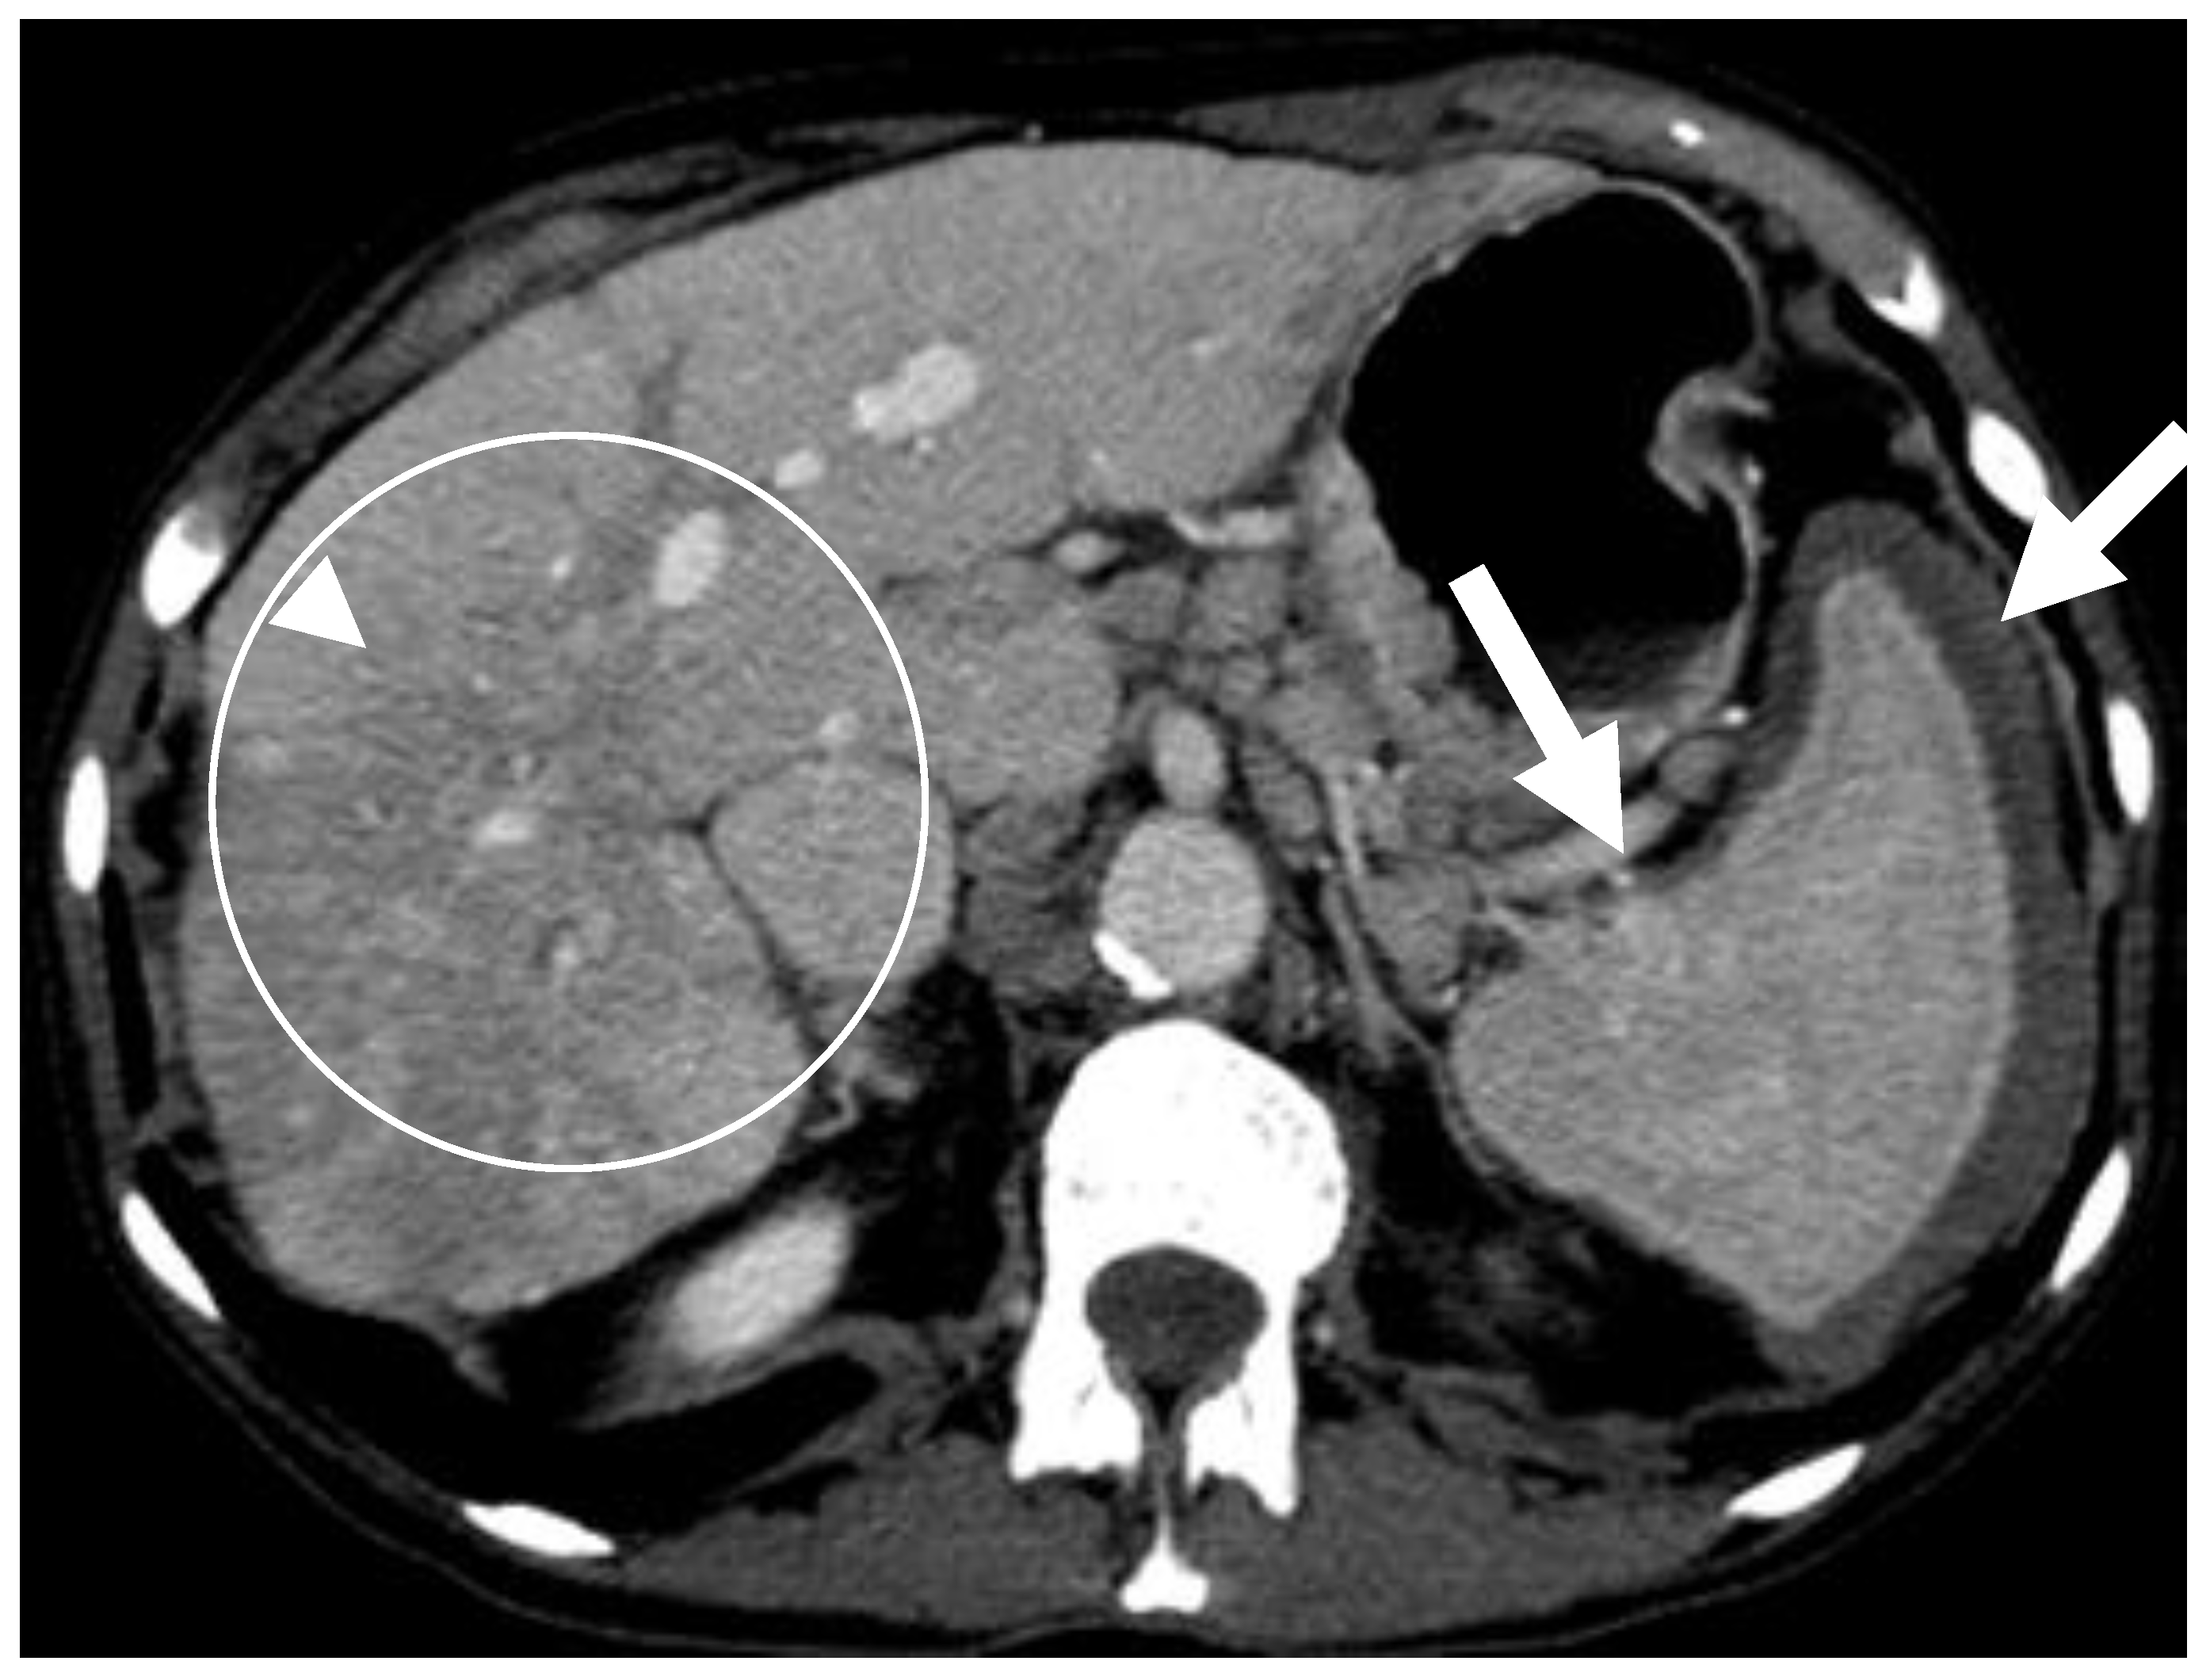

6.2. GI Tract, Liver and Spleen

6.2.2. Liver and Spleen

- Avila, N.A.; Ling, A.; Worobec, A.S.; Mican, J.A.M.; Metcalfe, D.D. Systemic mastocytosis: CT and US features of abdominal manifestations. Radiology 1997, 202, 367–372. [Google Scholar] [CrossRef] [PubMed]

- Narayanan, M.N.; Liu Yin, J.A.; Azzawi, S.; Warnes, T.W.; Turck, W.P.G. Portal hypertension and ascites in systemic mastocytosis. Postgrad. Med. J. 1989, 65, 394–396. [Google Scholar] [CrossRef] [PubMed] [Green Version]